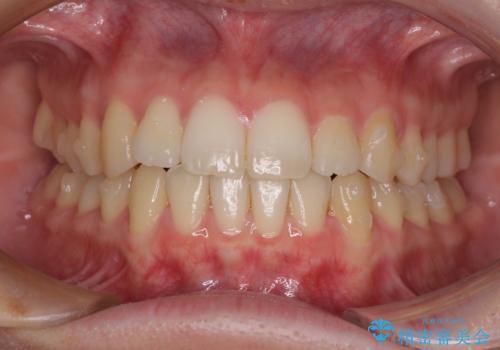

- ちょっとしたデコボコを整えたいとのことで来院された患者様です。

歯列不正は軽微であったため、インビザライン・ライトにより、費用を抑えて矯正治療を行うこととしました。